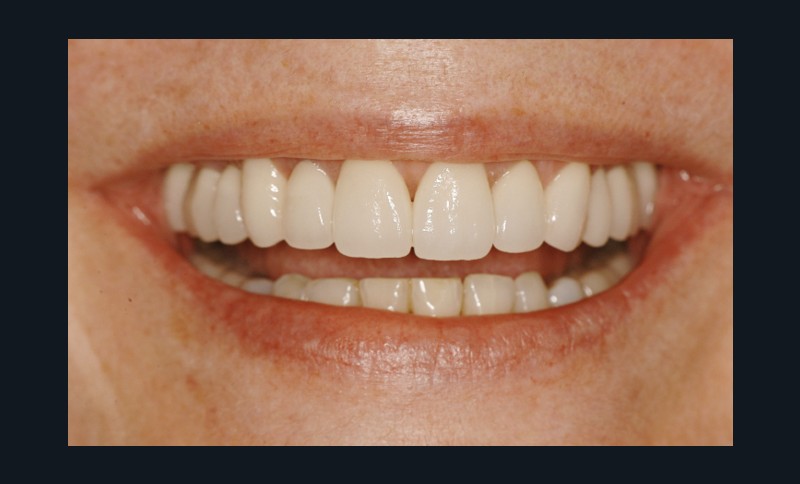

Car ce sont bien des situations cliniques exceptionnelles que ce conférencier a prises en charge, non pas seul, mais en constituant une équipe multidisciplinaire plus à même de relever les défis fonctionnels, structurels, biologiques et esthétiques en présence. Après avoir passé en revue les composants essentiels à l’obtention d’un sourire équilibré, Nadim Aboujaoude a évoqué les travers des traitements dits esthétiques mais conduits sans planification globale et qui engendrent des résultats disgracieux. Depuis de nombreuses années, l’engouement pour les solutions esthétiques ne faiblit pas. La divulgation médiatique des progrès technologiques et chirurgicaux réels encourage une part croissante de la population à recourir à des procédures souvent fiables, mais parfois portées au-delà des limites raisonnables. Ainsi, des traitements de médecine esthétique inadaptés engendrent un effet de « ligne de sourire basse » accompagné d’une exposition exagérée des incisives mandibulaires.

La demande de correction de cette anomalie esthétique incite les patientes à rechercher une compensation prothétique (à travers un abaissement des bords incisifs maxillaires visant à rendre sa visibilité au groupe incisivo-canin maxillaire) qui concoure à recomposer les rapports des étages de la face (en minorant l’étage inférieur et majorant l’étage moyen). La reprise de ces cas cliniques se révèle particulièrement délicate et repose sur une analyse rigoureuse des clefs esthétiques de l’harmonie du sourire et de son rayonnement au sein du visage.